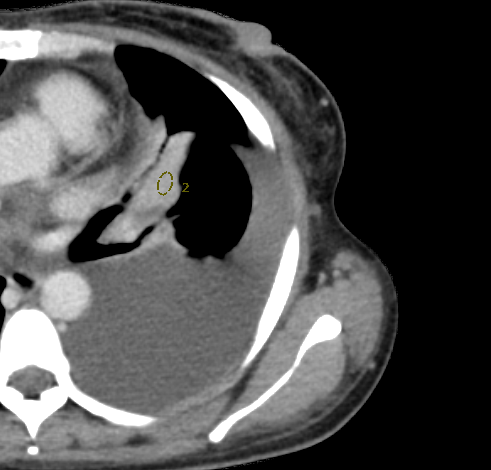

图二:女性,58岁,临床诊断:心律失常,心率 50-215 bpm

突破传统冠脉检查对心率的限制,即使心率高达200bpm或存在房颤、房扑,也能通过一次心跳捕捉心脏全貌。结合AI冠脉运动追焦技术,有效校正运动伪影,确保诊断精准。